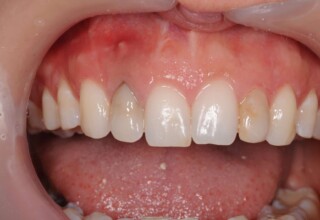

Αποκατάσταση διαστημάτων μεταξύ κεντρικών και πλαγίων τομέων

Τα διαστήματα έχουν δημιουργηθεί κυρίως λόγω των στενών πλαγίων. Μετά την ολοκλήρωση της ορθοδοντικής θεραπείας τα διαστήματα “έκλεισαν” με την τοποθέτηση δύο αποκαταστάσεων σύνθετης ρητίνης.